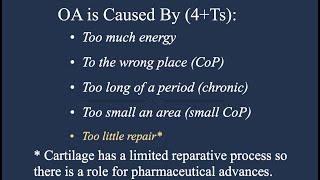

Osteoarthritis (OA) is Not From Aging#prevention#gait#sedentary#knee#back#kinetic#chain#movement

Mark Brezinski MD,PhD,CPT

62

205

2 года назад

Subtle Gait Abnormalities and Sitter's Disease as the Origin of Osteoarthritis: #Prevention#Gait#OA

Mark Brezinski MD,PhD,CPT

45

150

2 года назад